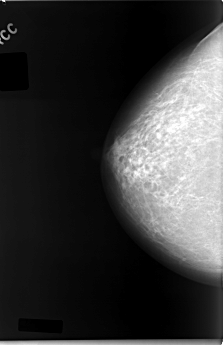

C_0038_1.RIGHT_CC

RIGHT_CC LINES 5864 PIXELS_PER_LINE 3808 BITS_PER_PIXEL 12 RESOLUTION 50 NON_OVERLAY